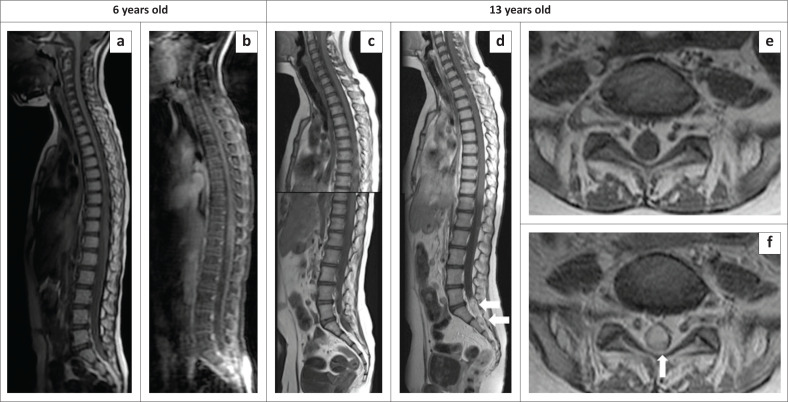

Leptomeningeal dissemination is a rare manifestation of pilocytic astrocytoma. It may occur with higher-grade tumours like medulloblastoma, ependymoma and high-grade glioma, but is extremely rare with low-grade glioma. There has been a growing number of reported cases documenting leptomeningeal dissemination of pilocytic astrocytoma in the medical literature.

Contribution: Description of a World Health Organization (WHO) Grade I suprasellar pilocytic astrocytoma with leptomeningeal dissemination in the brain and spinal cord which showed progression of the leptomeningeal nodules without tumour upgrading on long-term follow-up.